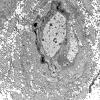

5B7 (Case 5) EM 021 - Copy